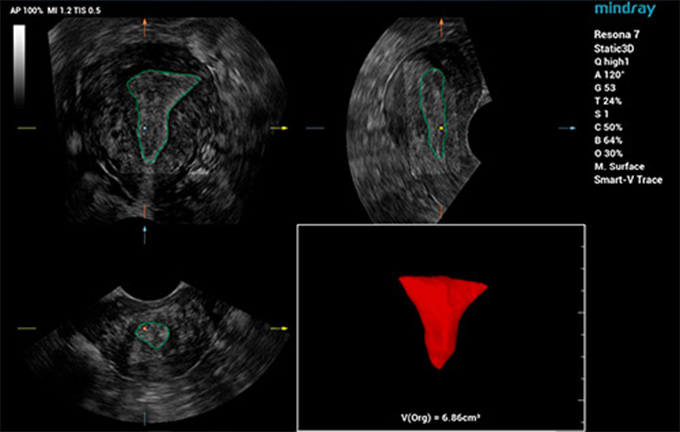

L'Êvaluation de l'emplacement et de la morphologie de l'ensemble des structures tissulaires pelviennes et du hiatus des releveurs constitue l'objectif principal de l'examen Êchographique du plancher pelvien. Cependant, l'examen manuel traditionnel est chronophage et dÊpend de l'opÊrateur, et les Êchographistes inexpÊrimentÊs rencontrent souvent des difficultÊs de localisation. Parallèlement, l'inefficacitÊ de la procÊdure d'imagerie peut multiplier la gêne et l'inconfort pour les patientes. Avec la sensibilisation croissante à la santÊ du plancher pelvien des femmes, il est prÊvisible que la demande d'examens du plancher pelvien par Êchographie augmente. Il est donc impÊratif de dÊvelopper une mÊthode de diagnostic du plancher pelvien par Êchographie plus exacte, plus efficace et plus simple à utiliser.

Mindray a dÊveloppÊ Smart Pelvic, une solution intelligente d'Êchographie du plancher pelvien pour aider les Êchographistes à obtenir rapidement des coupes et des mesures standardisÊes lors d'examens complexes du plancher pelvien et pour amÊliorer l'efficacitÊ du diagnostic. Smart Pelvic peut effectuer automatiquement des mesures pelviennes complètes et offrir une imagerie?3D automatique du hiatus des releveurs, ainsi que des mesures du diamètre longitudinal, du diamètre transversal, de la superficie du hiatus des releveurs et de la taille de la lacune urÊtrale des releveurs. Les Êchographistes peuvent obtenir des donnÊes cliniques complètes pour une Êvaluation exacte en quelques interactions simples, nÊcessitant seulement un tiers du temps des examens traditionnels. En outre, Mindray propose trois normes industrielles principales qui prennent en charge diffÊrents types de sondes et permettent un fonctionnement standardisÊ.

Smart Pelvic